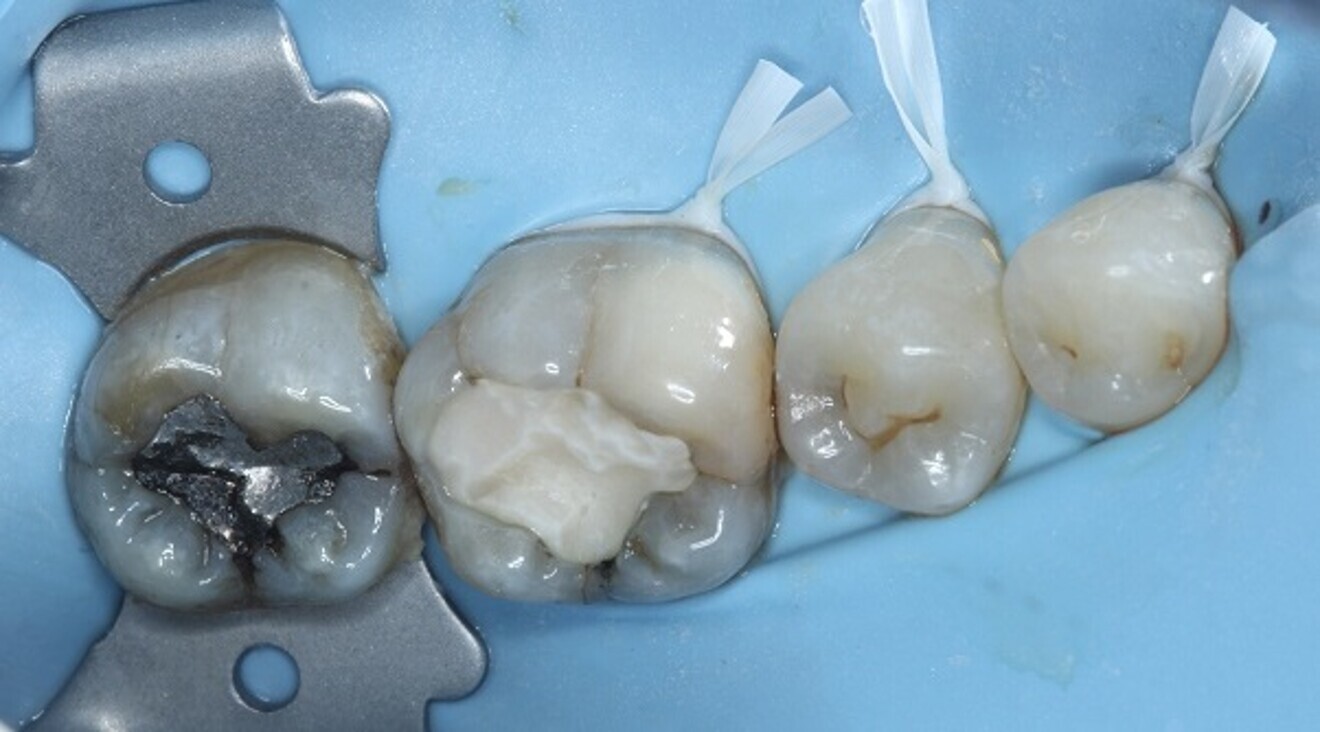

The canals were dried with paper points, a calcium hydroxide paste was placed in the canals and PTFE tape was used in the pulp chamber space. In order to improve the fracture resistance of the tooth in between appointments, deep marginal elevation was carried out with composite for the mesial marginal ridge, utilising a band-in-band technique. The tooth was temporarily restored with a glass ionomer cement, and the occlusion and contacts checked (Figs. 6–8).

Fig. 6: Band-in-band technique using a sectional matrix within a deep marginal elevation band to restore the marginal ridges.

Fig. 7: After deep marginal elevation and restoration of the marginal ridges of tooth #36.